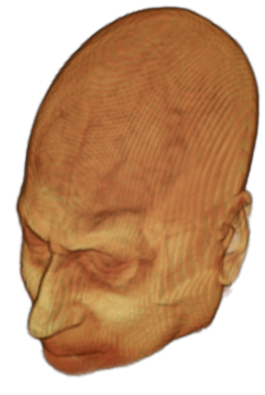

The digitalization of heath records has increased the risk of –and impact of– large scale data leaks. Although data compliance standards have been enacted to protect health records (HIPAA and GDPR), privacy of medical data is a growing concern. Three-dimensional scans such as magnetic resonance images (MRI) and computed tomography (CT), for example, contain an intrinsic privacy risk [Lotan et al.(2020)Lotan, Tschider, Sodickson, Caplan, Bruno, Zhang, and Lui]. Detailed renderings of the head can be crafted from 3D scans using techniques such as volumetric raycasting, as in Figure 1. This vulnerability can expose the patient’s identity if the renderings are matched to a face database [Mazura et al.(2012)Mazura, Juluru, Chen, Morgan, John, and Siegel, Lotan et al.(2020)Lotan, Tschider, Sodickson, Caplan, Bruno, Zhang, and Lui].

Therefore, in this work, we define a new class of de-identification techniques that remodels the privacy-sensitive regions without altering the content of medically relevant data (see Figure 1). Under such a remodeling approach, the face, eyes, oral and nasal cavities, etc. should exhibit realistic appearance and structure of appropriate size, but should otherwise be independent of the original data. To solve this task, we propose a novel model called Convex Privacy GAN, or CP-GAN, that conditions on a convex hull of the skull extracted from the scan to be de-identified. The generator learns to synthesize volumes that preserve medically-sensitive regions such as the brain, while non-invertibly remodeling privacy-sensitive characteristics from the original scan.